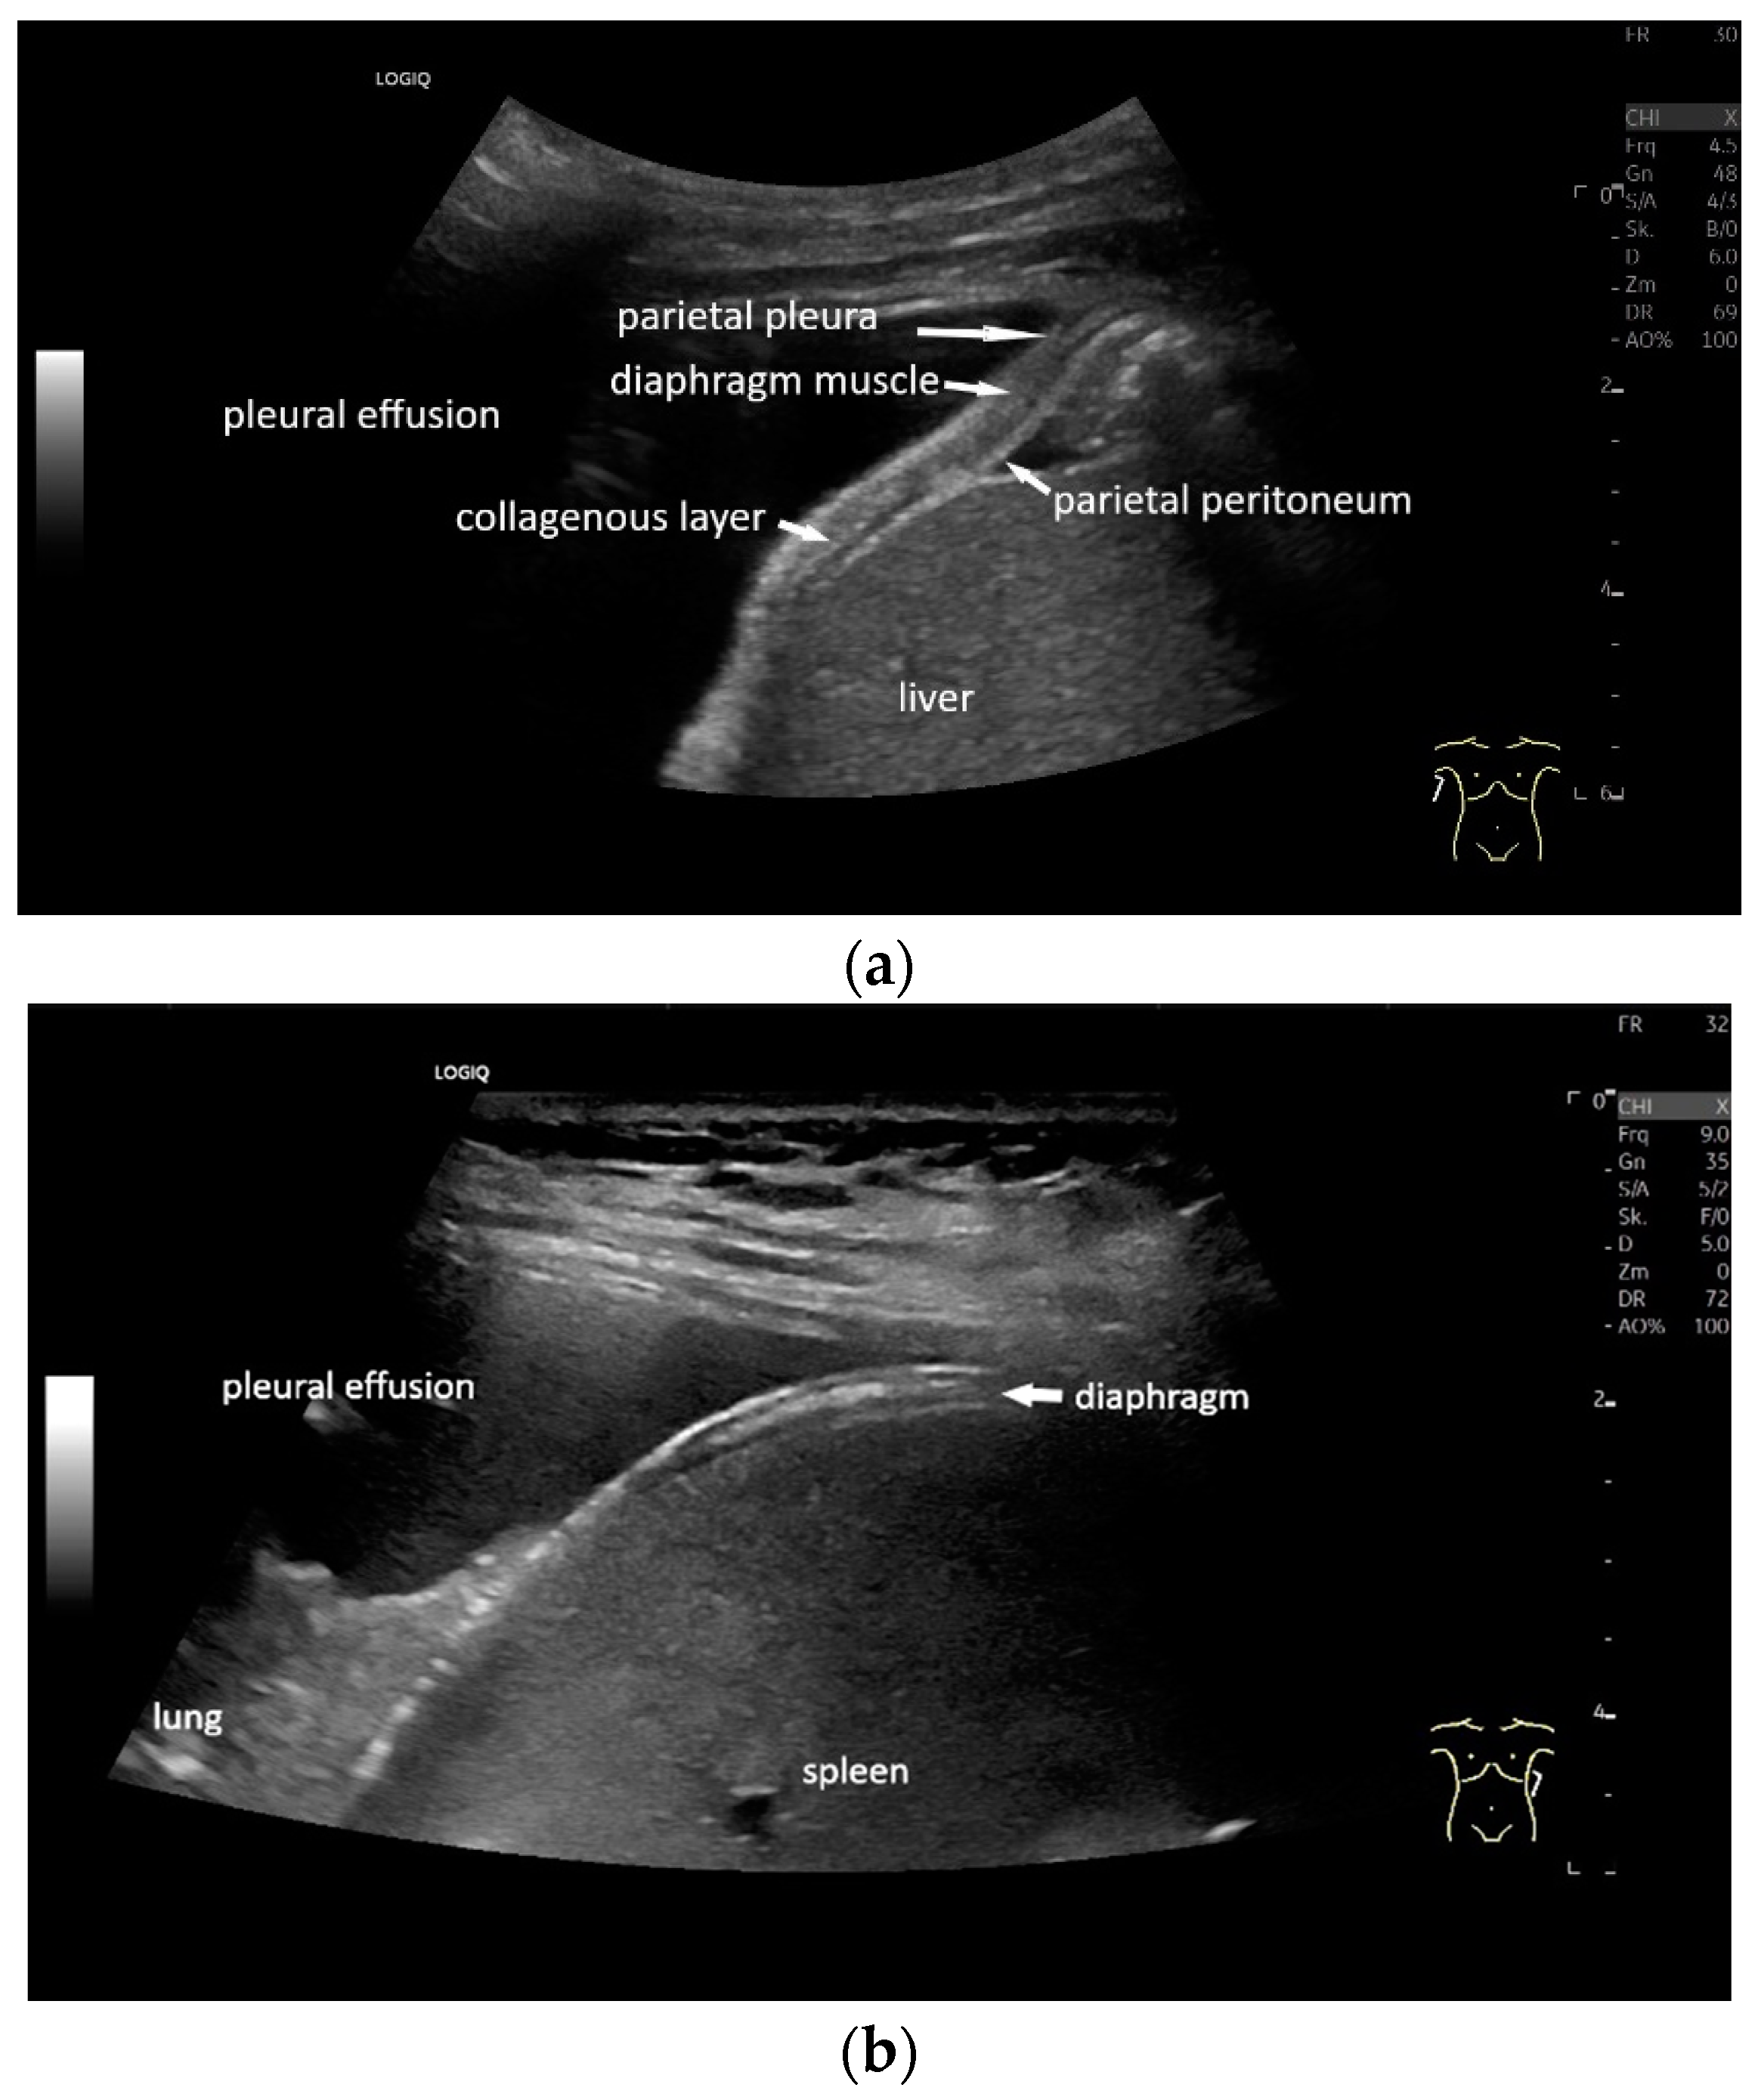

With high-resolution linear transducers, the diaphragm presents itself as a hypoechoic band. It is covered on both sides by a very thin hyperechoic layer. This corresponds to the peritoneum and the parietal pleura, respectively. Depending on the resolution, a further delicate hyperechoic layer is usually visible centrally in the muscle, which is most often considered to be a fibrous layer in the center of the diaphragm (Figure 1).

2. Diaphragm Anatomy

The diaphragm is a dome-shaped muscle that separates the abdominal cavity from the thoracic cavity. The central tendon of the diaphragm, a tendon around which the muscle fibers are arranged, is located centrally. Ventrally, the sternal part arises on the back of the xiphoid process. Dorsally, the lumbar part originates from the spinal column, and laterally, the costal part is attached to the inner sides of the cartilage of the lower six ribs. The diaphragm is the most important respiratory muscle and performs an estimated 75% of the inspiratory muscle work. When the diaphragm contracts during inspiration, the diaphragmatic dome flattens and the thoracic cavity enlarges. This creates negative pressure, which causes the lungs to expand. At the same time, the pressure in the abdominal cavity increases. The diaphragm is covered by the peritoneum on the abdominal side and by the parietal pleura on the thoracic side.

Lateral transducer position in the zone of apposition: The transducer is positioned longitudinally and laterally in the area of the mid-axillary line or slightly ventral to it between the anterior and mid-axillary lines, approximately in the 8th or 10th intercostal space. The diaphragmatic reflex is located on the inner side of the ribs below the pulmonary glide with pulmonary reverberations. This localization of origin of the diaphragm from the inner side of the rib cartilage is referred to as the zone of apposition (Figure 3). As this localization is only a few centimeters below the skin surface, high-resolution linear transducer use is highly recommended. In this position, the diameter of the diaphragm is measured during inspiration and expiration [2,3,4,5] (Figure 4). The thickness of the diaphragm varies, with caudal parts being thicker than cranial parts. The measurement of diaphragm thickness is highly variable depending on the intercostal space chosen, with thickness varying by up to 6 mm between the intercostal spaces [6]. It is therefore important to select the same position for comparable measurements and, if necessary, to mark the location for the transducer position [7]. Obesity limits assessment of the diaphragm [2].